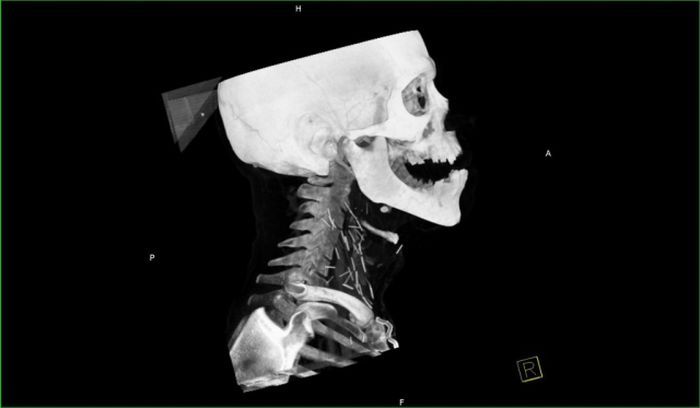

Рентген показал, что у чувака в шее огромное количество иголок.

Оказалось, что товарищ - нарк со стажем и все эти иглы остались в шее после неаккуратных инъекций.